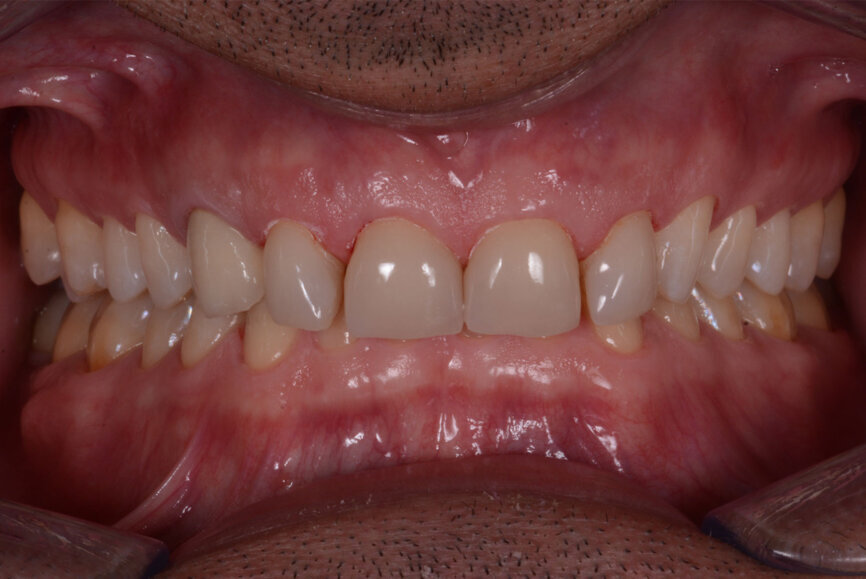

Fig. 13: Intraoral photographs after treatment.

Figs 14: Intraoral photographs after treatment.

Excess luting material was removed, and the occlusion was adapted and checked with the T-Scan technology (Tekscan). A removable acrylic resin splint was used to protect the final restorations. The final restorations were checked after six months. The restorations were still stable and showed no signs of fracture (Figs. 13–15). The patient also reported that he no longer suffered from headaches with the new bite height.